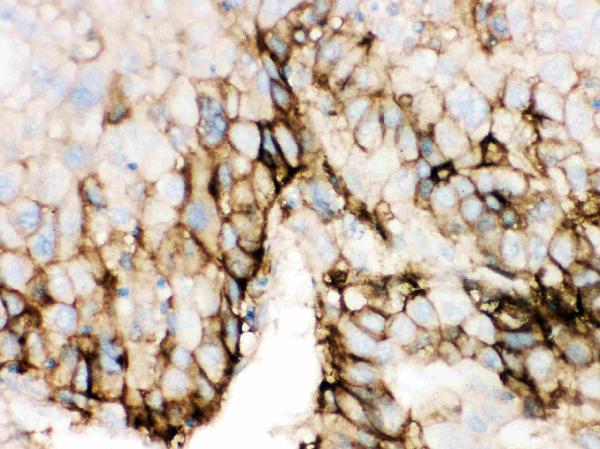

ApplicationsWestern Blot, ImmunoHistoChemistry

- ApplicationsWestern Blot, ImmunoHistoChemistry

- Scientific DescriptionBoster Bio Anti-Glucose Transporter GLUT2/SLC2A2 Antibody Picoband® catalog # PB9436. Tested in IHC, WB applications. This antibody reacts with Human. The brand Picoband indicates this is a premium antibody that guarantees superior quality, high affinity, and strong signals with minimal background in Western blot applications. Only our best-performing antibodies are designated as Picoband, ensuring unmatched performance.